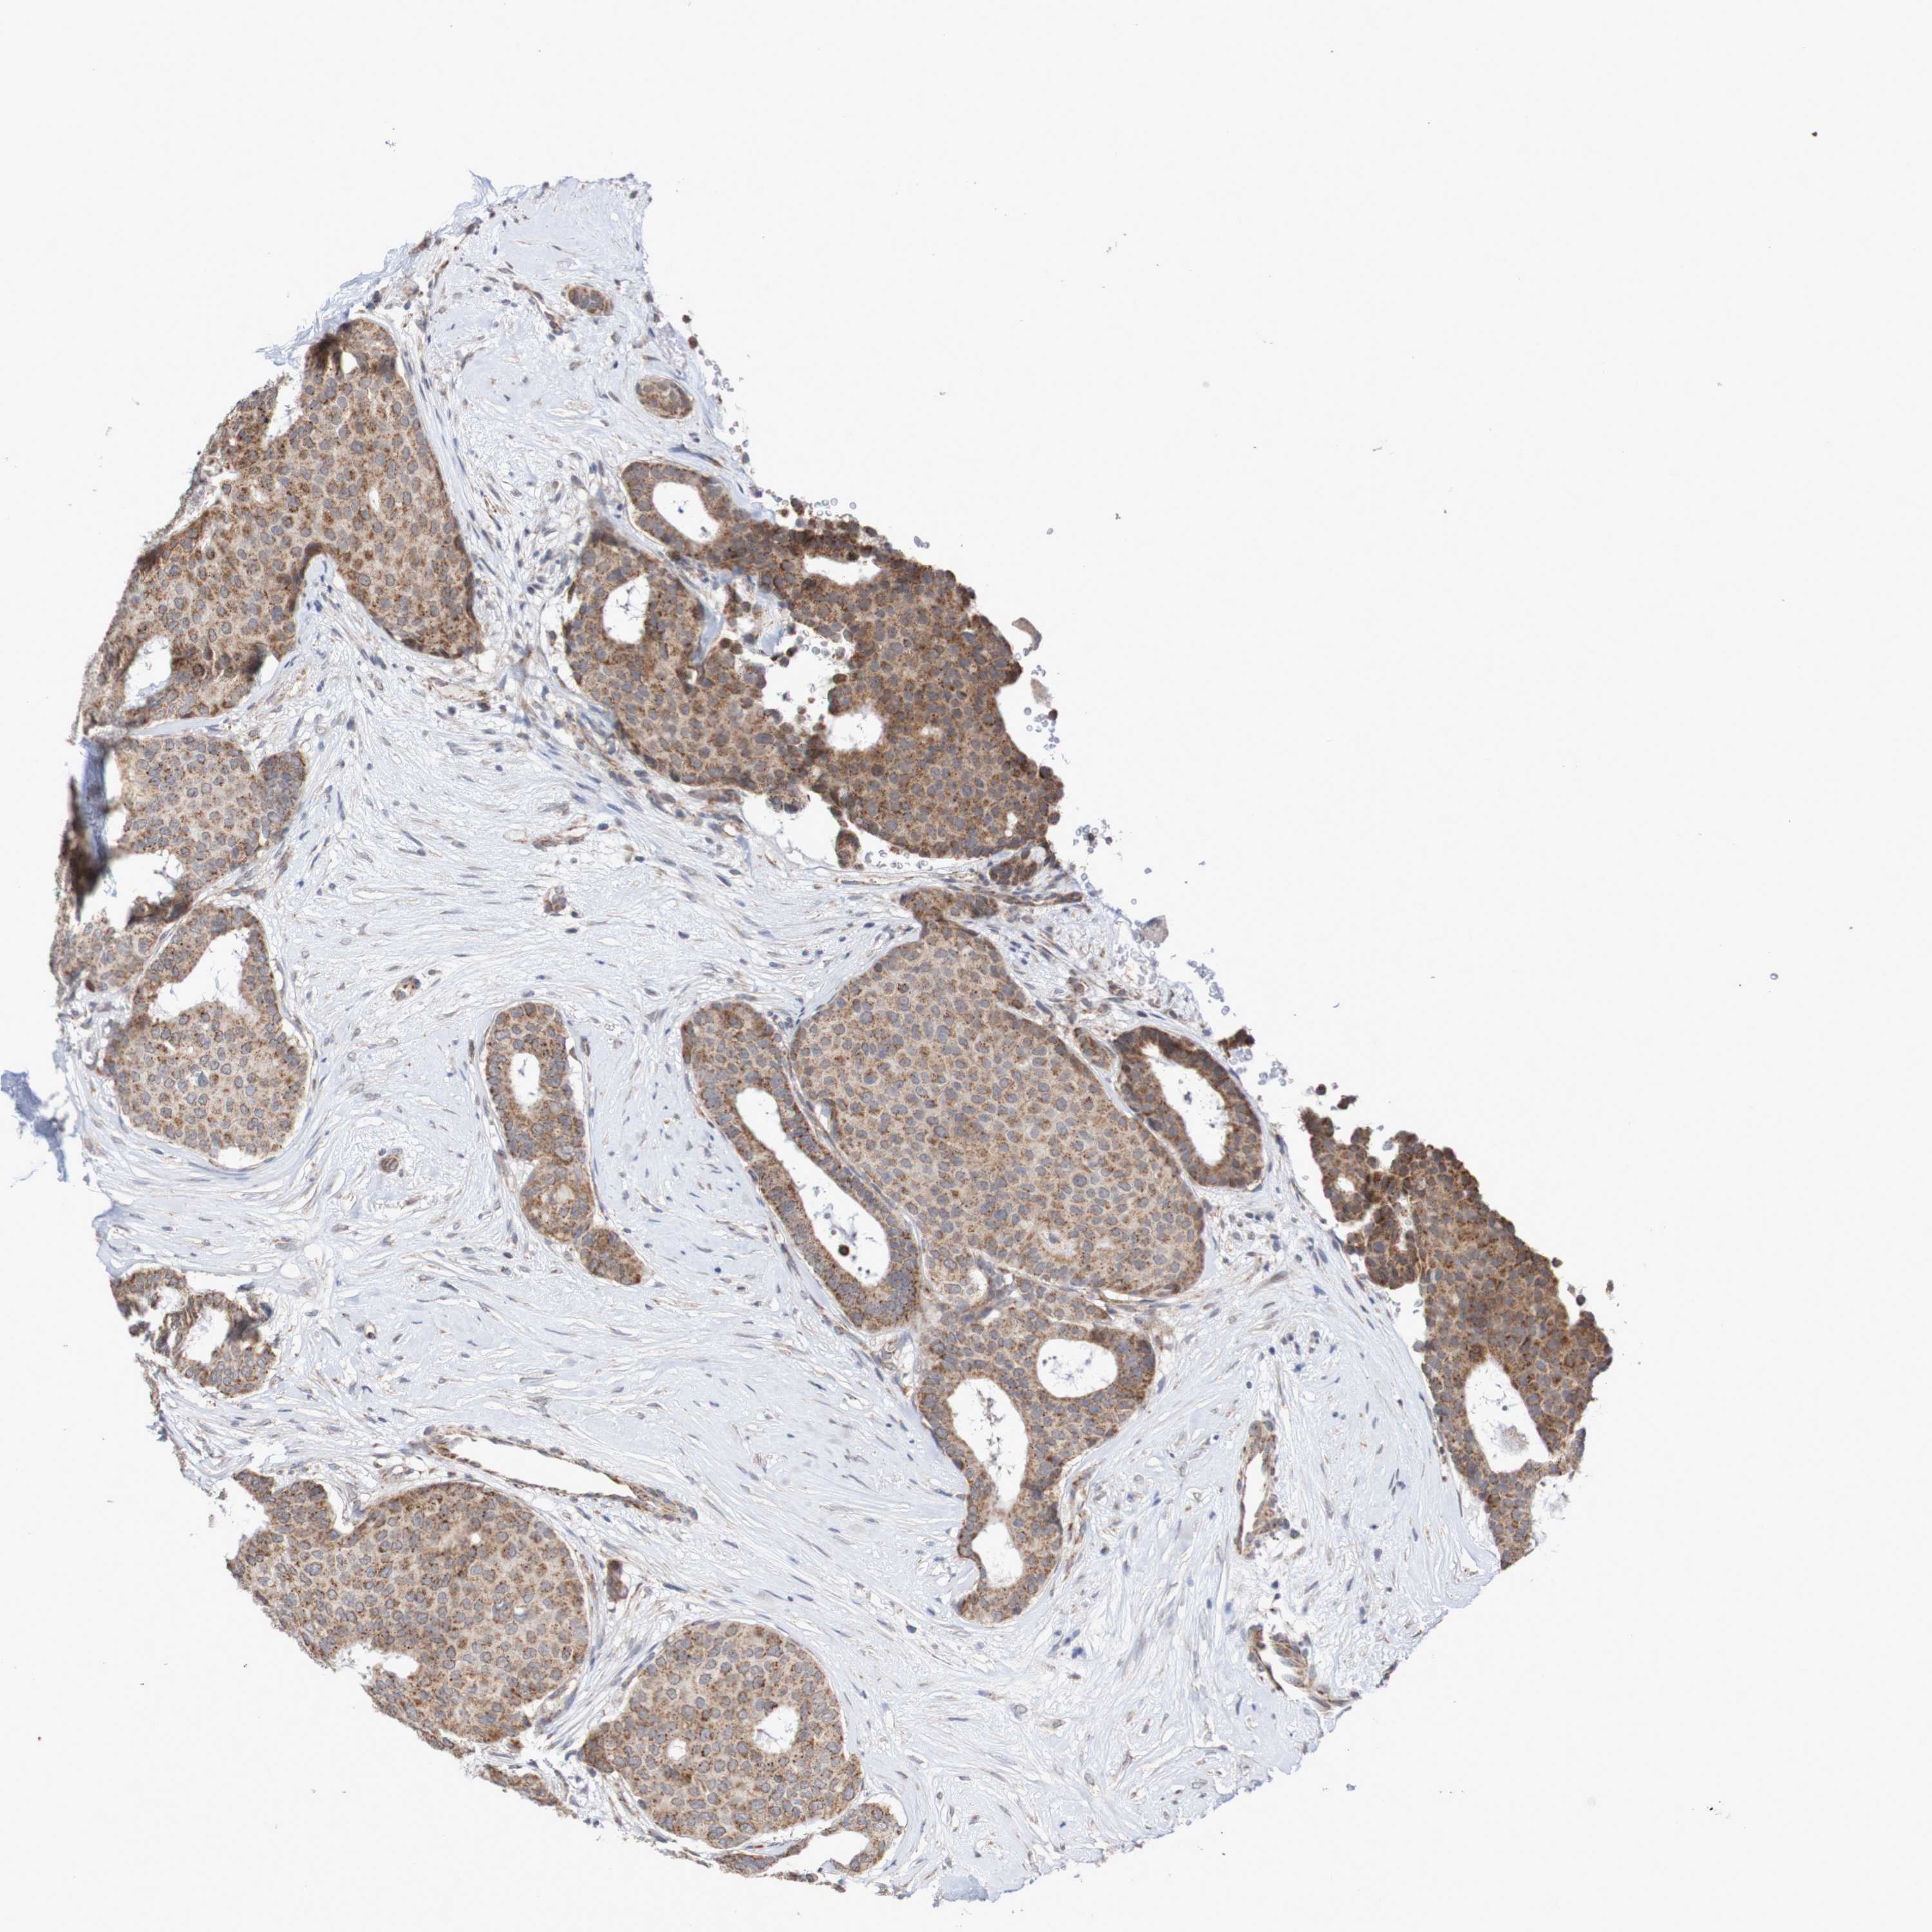

CANCER BREAST CANCER Show tissue menu

BRCA TCGA BRCA VALIDATION PROTEIN EXPRESSION